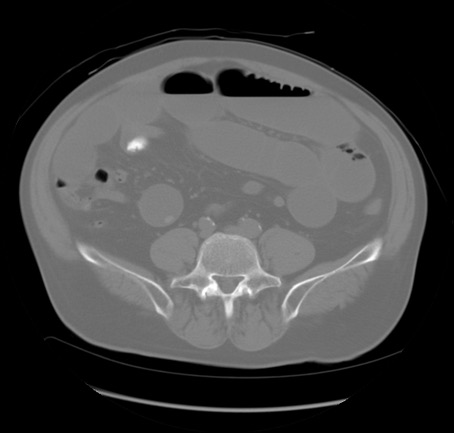

症例20(横断像)

【症例】 60歳代男性

【主訴】 腹部膨満、嘔吐

【現病歴】5日前頃より倦怠感を認め食事量減少し4日前の朝嘔吐、食事摂取困難となった。 3日前近医受診し点滴施行され整腸剤などを処方された。 当日他院を受診し、腹部膨満著明、炎症反応の上昇(CRP10.8、WBC11200)あり、紹介受診となる。

【身体所見】 意識JCS1 受け答えがはっきりしないBP 111/57mHg、 P 67bpm、、BT35.2°C、SpO2 97%(RA)、 腹部:膨隆、打診で鼓音あり、全体的に圧痛有り、腸蠕動音(-)、反跳痛ははっきりせず。

【データ】WBC 11400、CRP 14.20